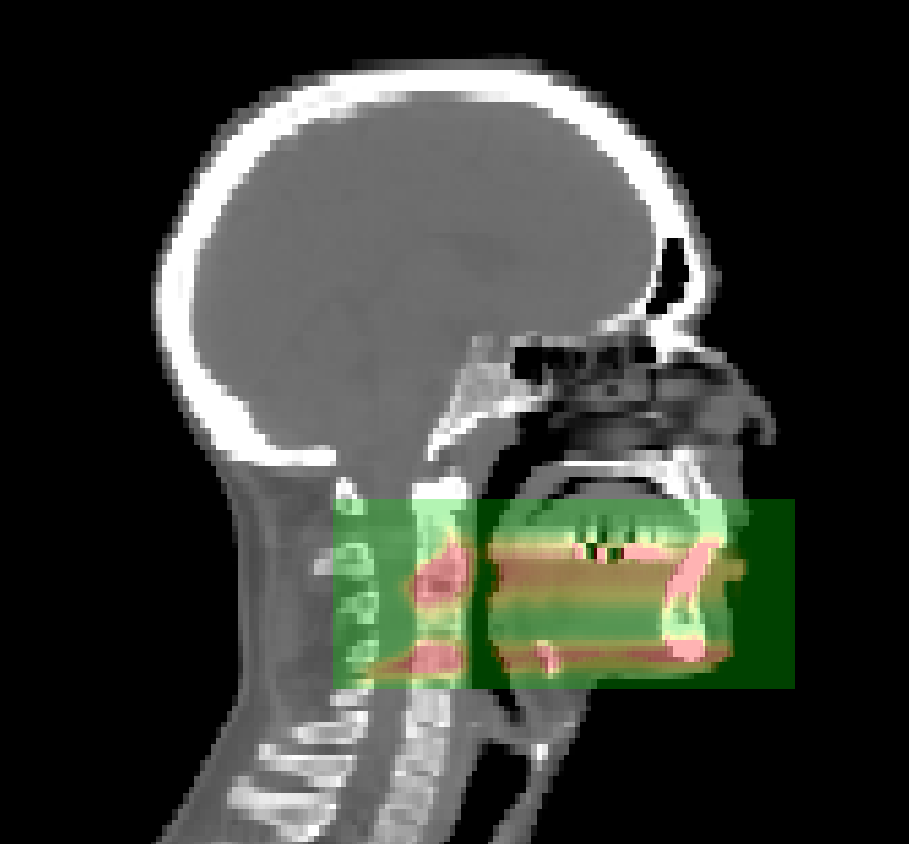

PIC

Figure 4: Sagittal view of the patient CT image, illustrated with the PG yield caused by the associated treatment plan. A beam from an original treatment plan has been rotated to align with the image axes, to both make projections easier and to increase the heterogeneity of the materials and thereby increase the challenge to vpgTLE. The applied radiation is the distal layer of one of the beams of the original plan so that the distal falloff is better defined in contrast to the spread out Bragg Peak (SOBP). The voxel size is again 23 mm3.